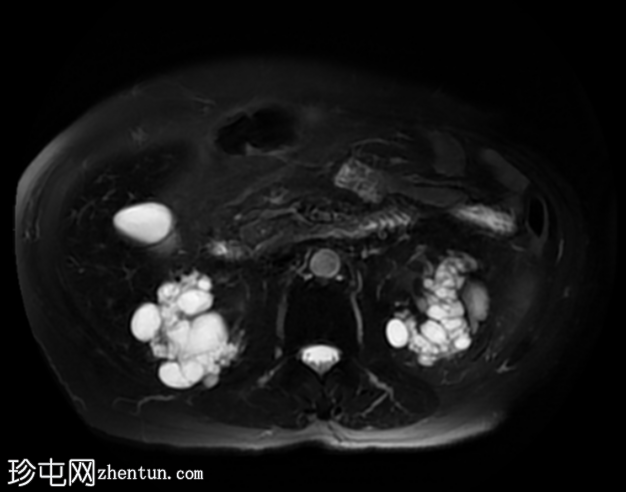

轴位

STIR序列

双侧肾囊性疾病,可见多个肾囊肿,其中许多呈复杂性(出血性)囊肿,T1加权像呈高信号,T2加权像呈低信号。

左侧可见一较大的肾周血肿,与上极出血性囊肿相连,提示出血性囊肿破裂(Wunderlich综合征)。

未见肾脏软组织肿块。

轻度肝脾肿大,受检骨骼T2加权像呈弥漫性低信号,提示肾性骨营养不良。